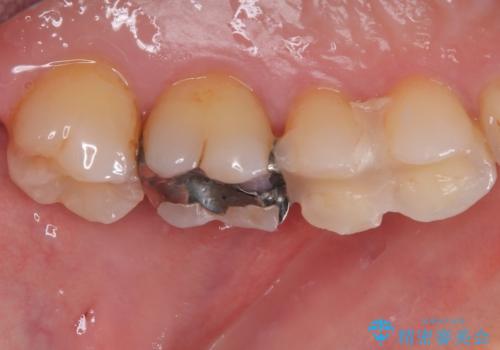

- 銀歯が取れたとのことで来院された患者様です。患者様の歯をあまり削りたくないというご希望に添い、セラミックインレーにて治療を行うこととなりました。

拡大鏡視野下で、保険のプラスチック、虫歯の除去を行い、セラミックインレーに適した形に整えました。

歯と歯茎の間に圧排糸と言われる糸を入れてシリコーン印象材にて精密な型どりをしました。